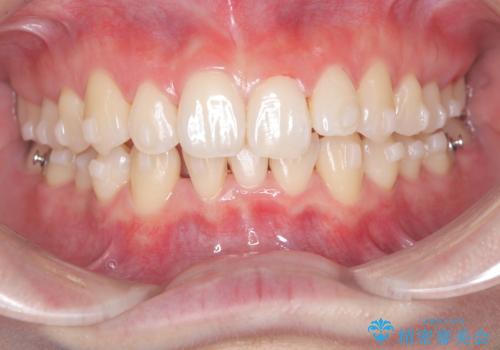

- 患者様は、下顎前歯のガタつきを改善したいとのことで来院されました。診察の結果、スペース不足により前歯が重なっている状態でした。抜歯をせずに並べると前歯が前方に突出してしまうため、下顎の前歯を1本抜歯し、インビザラインで矯正する治療計画を立てました。できる限り追加のアライナーを使用せずに治療を完了できるよう、初回の治療計画を慎重に設計しました。

下顎前歯を1本抜歯し、歯列のスペースを確保。その後、インビザラインを用いて計画通りに歯を移動させ、噛み合わせも整えました。患者様の協力もあり、ゴムかけなどを適切に行い、予定通り1年で治療を完了。追加アライナーを使用することなく、計画通りに治療を終えることができました。患者様からは「思ったより早く終わり、仕上がりにも満足している」と喜びの声をいただきました。